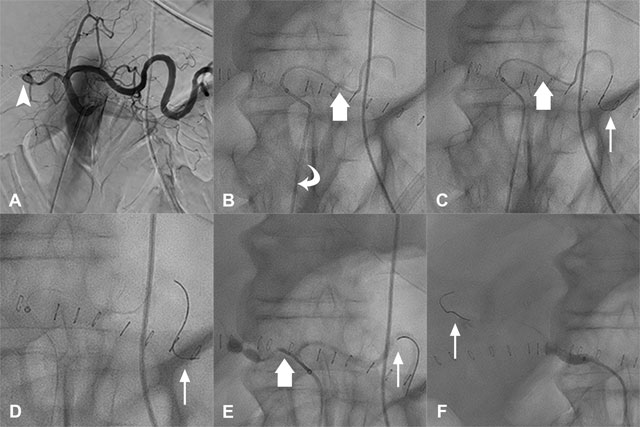

Figure 1

Details of the Parallel Guidewire Anchoring Technique. Angioplasty without stenting of the graft hepatic artery in a 70-year-old patient. A. Initial arteriography showed a graft hepatic artery stenosis (arrowhead). B. Catheterization was performed as distally as possible in the splenic artery with a catheter and a microcatheter (large arrow) through a long sheath (curved arrow). C. A stiff 0.014” guidewire (thin arrow) was introduced into the microcatheter (large arrow). D. The microcatheter and the catheter were completely removed. E. The catheter and the microcatheter (large arrow) were introduced in parallel of the stiff guidewire and used to catheterize the common hepatic artery. F. The stiff guidewire (thin arrow) was removed from the splenic artery to position the long sheath further into the graft hepatic artery.